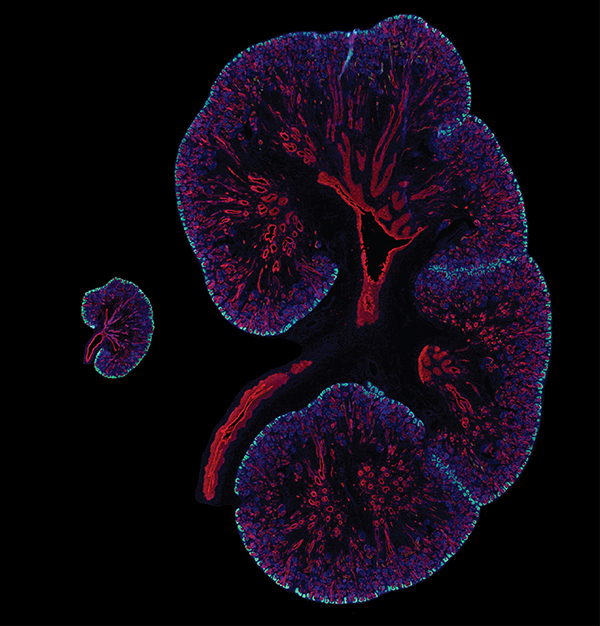

کشف کلیدی این پژوهش آن است که تودههای پروتئین آلفا-سینوکلئین نهتنها در مغز، بلکه در کلیهها نیز میتوانند تجمع پیدا کنند. پژوهشگران بر این باورند که این پروتئینهای غیرطبیعی ممکن است از کلیهها به مغز منتقل شوند و احتمالا در آغاز بیماری نقش داشته باشند.

ابعاد زیادی در این پژوهش قابل بررسی است. تیم تحقیقاتی مجموعهای از آزمایشها را انجام داد؛ از بررسی رفتار پروتئین آلفا-سینوکلئین در موشهای مهندسیشده ژنتیکی گرفته تا تحلیل نمونههای بافت انسانی، از جمله نمونههایی مربوط به افراد مبتلا به بیماری پارکینسون و بیماری مزمن کلیه. تیم پژوهشی دریافت که در کلیههای ۱۰ نفر از ۱۱ فرد مبتلا به پارکینسون و دیگر انواع زوال عقل مرتبط با اجسام لوی (نوعی تجمع رایج پروتئین آلفا-سینوکلئین)، رشد غیرطبیعی این پروتئین مشاهده شده است.

اما این همه ماجرا نبود: در یک گروه نمونه دیگر، اختلالات مشابه پروتئینی در ۱۷ نفر از ۲۰ بیمار مبتلا به بیماری مزمن کلیه مشاهده شد، با این که این افراد هیچ نشانهای از اختلالات عصبی نداشتند. این موضوع شواهد بیشتری فراهم میآورد که کلیهها محل اولیه تجمع این پروتئینهای مضر هستند، پیش از آن که آسیب به مغز آغاز شود.

آزمایشهای حیوانی نیز این فرضیهها را تأیید کردند. موشهای دارای کلیههای سالم توانستند تودههای آلفا-سینوکلئین تزریقی را پاکسازی کنند، اما در موشهایی که کلیههای آنها عملکرد نداشت، این پروتئینها تجمع پیدا کرده و در نهایت به مغز سرایت کردند. در آزمایشهای بیشتر، هنگامی که اعصاب بین مغز و کلیهها قطع شدند، این سرایت اتفاق نیفتاد.